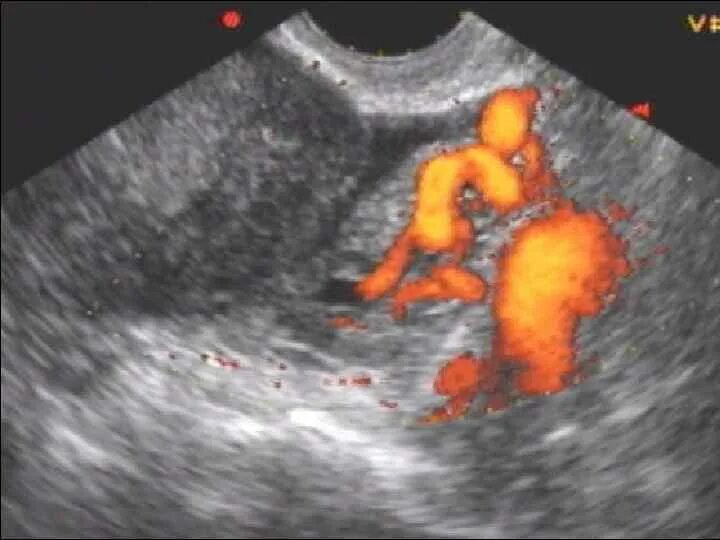

Тромб в матке